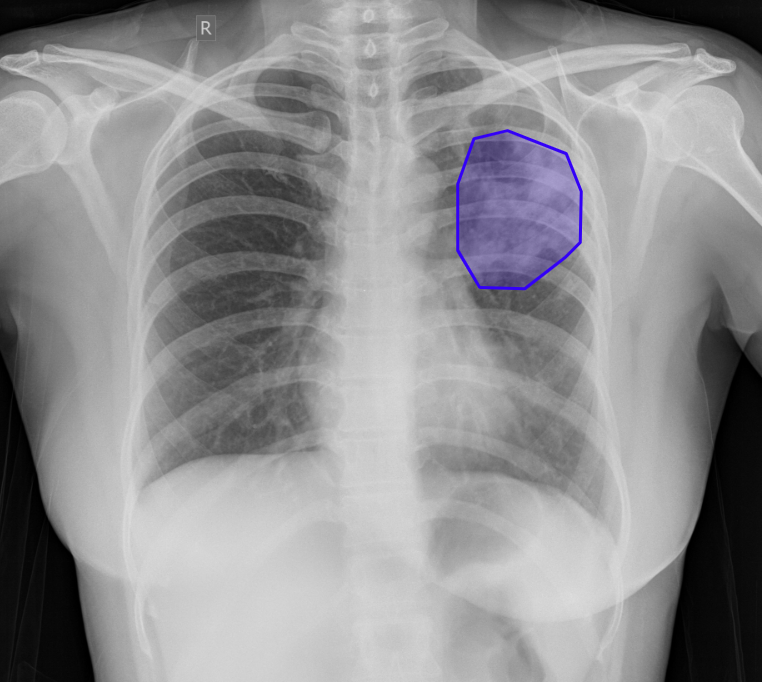

What does AI-detected pathology look like?

Eight examples of AI-annotated chest X-rays with color-coded pathology overlays

Chest X-ray with AI-detected Consolidation highlighted

Consolidation